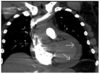

What are the features on this CXR?

Pleural effusion (in e.g heart failure, lungs so saturated that fluid accumulates in pleural space. A step worse from pulm oedema.

Pulmonary oedema (fluid in intersitium)

Large cardiothoracic ratio

Chest wires